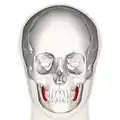

Bucinator outlined in red. | |

Position of buccinator muscle (red)

Position of buccinator muscle (red) -

Position of buccinator muscle (red)

Position of buccinator muscle (red) -

Position of buccinator muscle (red)

Position of buccinator muscle (red) -